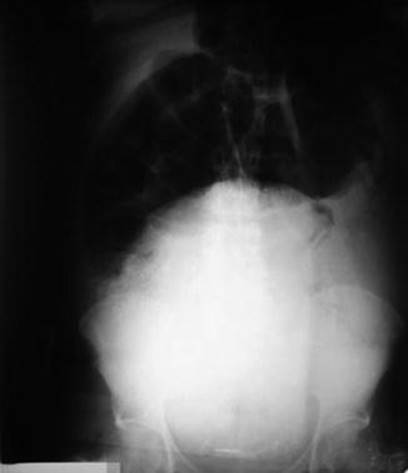

7.3.6 Diagnosis

The diagnosis should be suspected when air-liquid levels of small bowel are evident on plain abdominal X-ray. Knowledge of the typical appearance of the uterus after a first trimester surgical abortion is clearly helpful in recognizing an abnormal pelvic ultrasound. In the emergently presenting patient, ultrasound is the preferred diagnostic modality, but it should be recognized that the normal appearance of the uterus after a first trimester surgical abortion can be quite variable. A small number of imaging studies have documented the appearance of the uterus after a first trimester surgical abortion [145–147]. Dillon et al. [145] performed short-term follow-up with ultrasound to qualitatively evaluate the uterine cavity after a first trimester surgical abortion in 19 asymptomatic patients. In this study, 59 % of patients had a varying amount of intrauterine material, initially appearing hyperechoic and then later iso- or hypoechoic. No material seen resembled retained fetal parts or placental material. The time for the return of the endometrial stripe to baseline appearance was variable, ranging 1–14 days. Similarly, another larger study by Bar-Hava et al. [146] examined the appearance of the uterus of 74 women who had undergone a first trimester surgical abortion within 1 week of the procedure. Only 23 % of patients demonstrated reversion to a thin endometrial stripe, 50 % displayed a thick endometrial stripe (7–19 mm), and 27 % an endometrial stripe >20 mm or with very irregular echogenicity >14 mm. These investigators also described a trend toward hyperechoic endometrial contents earlier in the week versus hypoechoic contents later in the week, presumably due to liquefying endometrial contents. The appearance of endometrium after the first menstrual period reverted to normal in all patients. Patient demographics such as gravidity or date of first trimester abortion did not correlate with the appearance of the uterus.

Ultrasound appearance of uterine perforation with suspected bowel entrapment was first reported in 1983 by Dunner et al. [133]. Defect in the uterine wall could be detected with the transabdominal ultrasound. Tubular-shaped irregular tissue could be seen within the endometrial cavity, with a small echoic focus suggesting the presence of air (Fig. 7.19). An abnormally increased amount of echogenic free fluid could be seen in the cul-de-sac [131].

Fig. 7.19

(a, b) Transabdominal pelvic ultrasound images demonstrate a retroverted uterus (UT) adjacent to the urinary bladder (BL) with adjacent fluid-filled small bowel (SB) closely apposed to an interrupted uterine wall (asterisk). A tubular structure is seen within the uterus. A small amount of anechoic free fluid (FF) is seen in the cul-de-sac. Linear echogenicity (arrow), consistent with the appearance of gas, is adjacent to the abnormal intrauterine tubular structure [131]

Transvaginal sonography is a convenient tool in aiding in the diagnosis. Image findings of free fluid in the pelvis, loops of bowel within the myometrial wall, extrauterine fetal parts, or intraoperative presence of the curette within the myometrium have all been used to confirm uterine perforation [148]. Ultrasound of the pelvis could delineate bright, serpiginous, fluid-filled tubular structures within the endometrial cavity (Fig. 7.20). Adjacent material of increased echogenicity could be suggestive of fat. Color Doppler would not show blood flow in these structures, and no peristalsis would be seen in the intrauterine contents [131].

Fig. 7.20

(a) Transvaginal pelvic ultrasound transversely demonstrates multiple tubular structures containing anechoic fluid within the uterine cavity (UT); (b) sagittally, echogenic material (arrowheads), suggesting the presence of fat, is adjacent to the intrauterine tubular structure [131]

The first reported CT diagnosis of incarcerated bowel in a uterine perforation was by Dignac et al. (incarcerated appendix) and Chang et al. in 2008 [126, 127]. Evaluation with CT has an important diagnostic role in cases where ultrasound is ambiguous or if non-gynecologic pathology is suspected. Although the uterine wall can hinder visualization of intrauterine bowel loops, Dignac et al. emphasize that the bowel’s mesentery can be well visualized on CT scan due to its fatty nature and should be a red flag for intrauterine bowel [127]. CT scan can delineate bowel loops within the uterus (Fig. 7.21).

Fig. 7.21

Pelvic computed tomography scan taken after failure of conservative treatment. Intrauterine mass was later shown to be an incarcerated bowel [126]